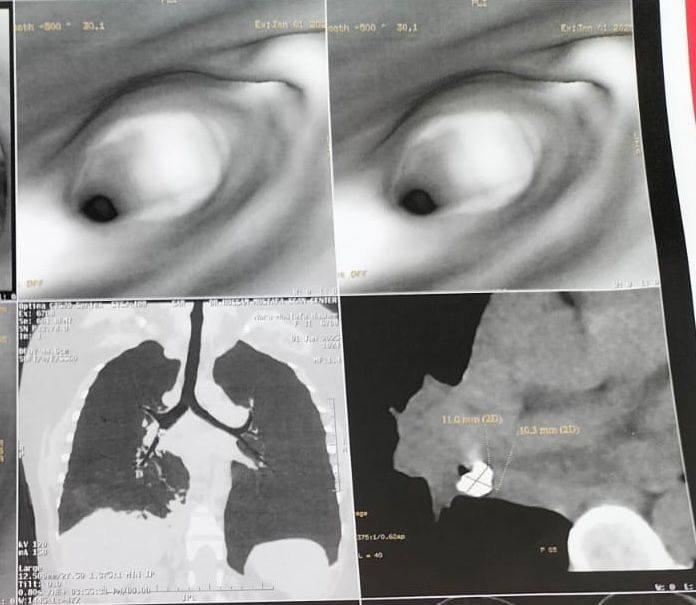

ليقوم الفريق الطبي بإجراء منظار و أشعة مقطعية تبين من خلالها وجود تكلسات وتليفات مزمنة داخل الشعب الهوائية الخاصة بالرئة اليمنى، الأمر الذي كان يتطلب استئصال جزئي او كلي للرئة، ليقرر الفريق الطبي إجراء تدخل جراحي غير معتاد في مثل هذا الحالات، حتى يتم تجنب استئصال جزء من رئة المريضة، وتعرضها لمضاعفات، وذلك عن طريق تدخل جراحي دقيق ومعقد، حيث تم استئصال التكلسات والتليف، مع الحفاظ الكامل على الرئة اليمنى واستعادتها لكامل وظيفتها.

وبالمتابعة وإجراء عدد من التحاليل لفحص الجسم الغريب، للتأكد من وجود أورام أم لا، تبين أن الجسم الغريب عبارة عن ضرس تم استنشاقه وتراكم عليه تكلسات وتليفات.